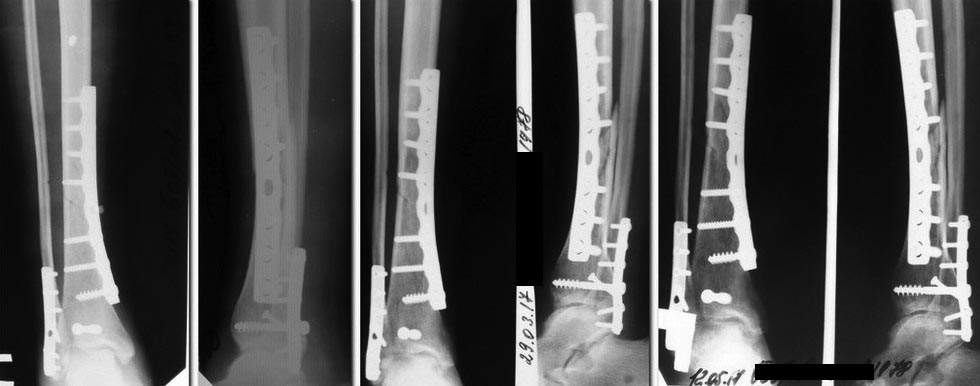

Уважаемые коллеги, помогите по тактике лечение. Девушка 39

лет,работающая, без вредных привычек, состояние после остеосинтеза

костей голени от 20.12.2017.

Травма бытовая 12.12.2016, 20.12.2017 выполнена открытая репозиция

остеосинтез большеберцовой кости пластиной, заднего края ДМЭ винтом,

синтез наружной лодыжки пластиной. Рентгенограмм до операции нет. До

прошлой недели ходила на костылях без нагрузки, принимала остеогенон.

В январе курс реабилитации. В настоящий момент клинически - отека нет,

п/о рубец без патологии, пальпация голени безболезненна. Движения в

коленном суставе в полном объеме, небольшое ограничение тыльной флексии

в голеностопном суставе.

Разрешена нагрузка 20-25 кг (до 50% массы тела), 3 дня в таком режиме -

новых жалоб не появилось. Мнения по дальнейшему ведению разделились. 1

вариант - продолжить ЛФК, физиолечение, медикаментозную терапию с

дозированной нагрузкой. Подождать до еще хотя бы 3 мес. 2 вариант -

оперативное лечение с костной пластикой. Подскажите, кто бы как поступил?